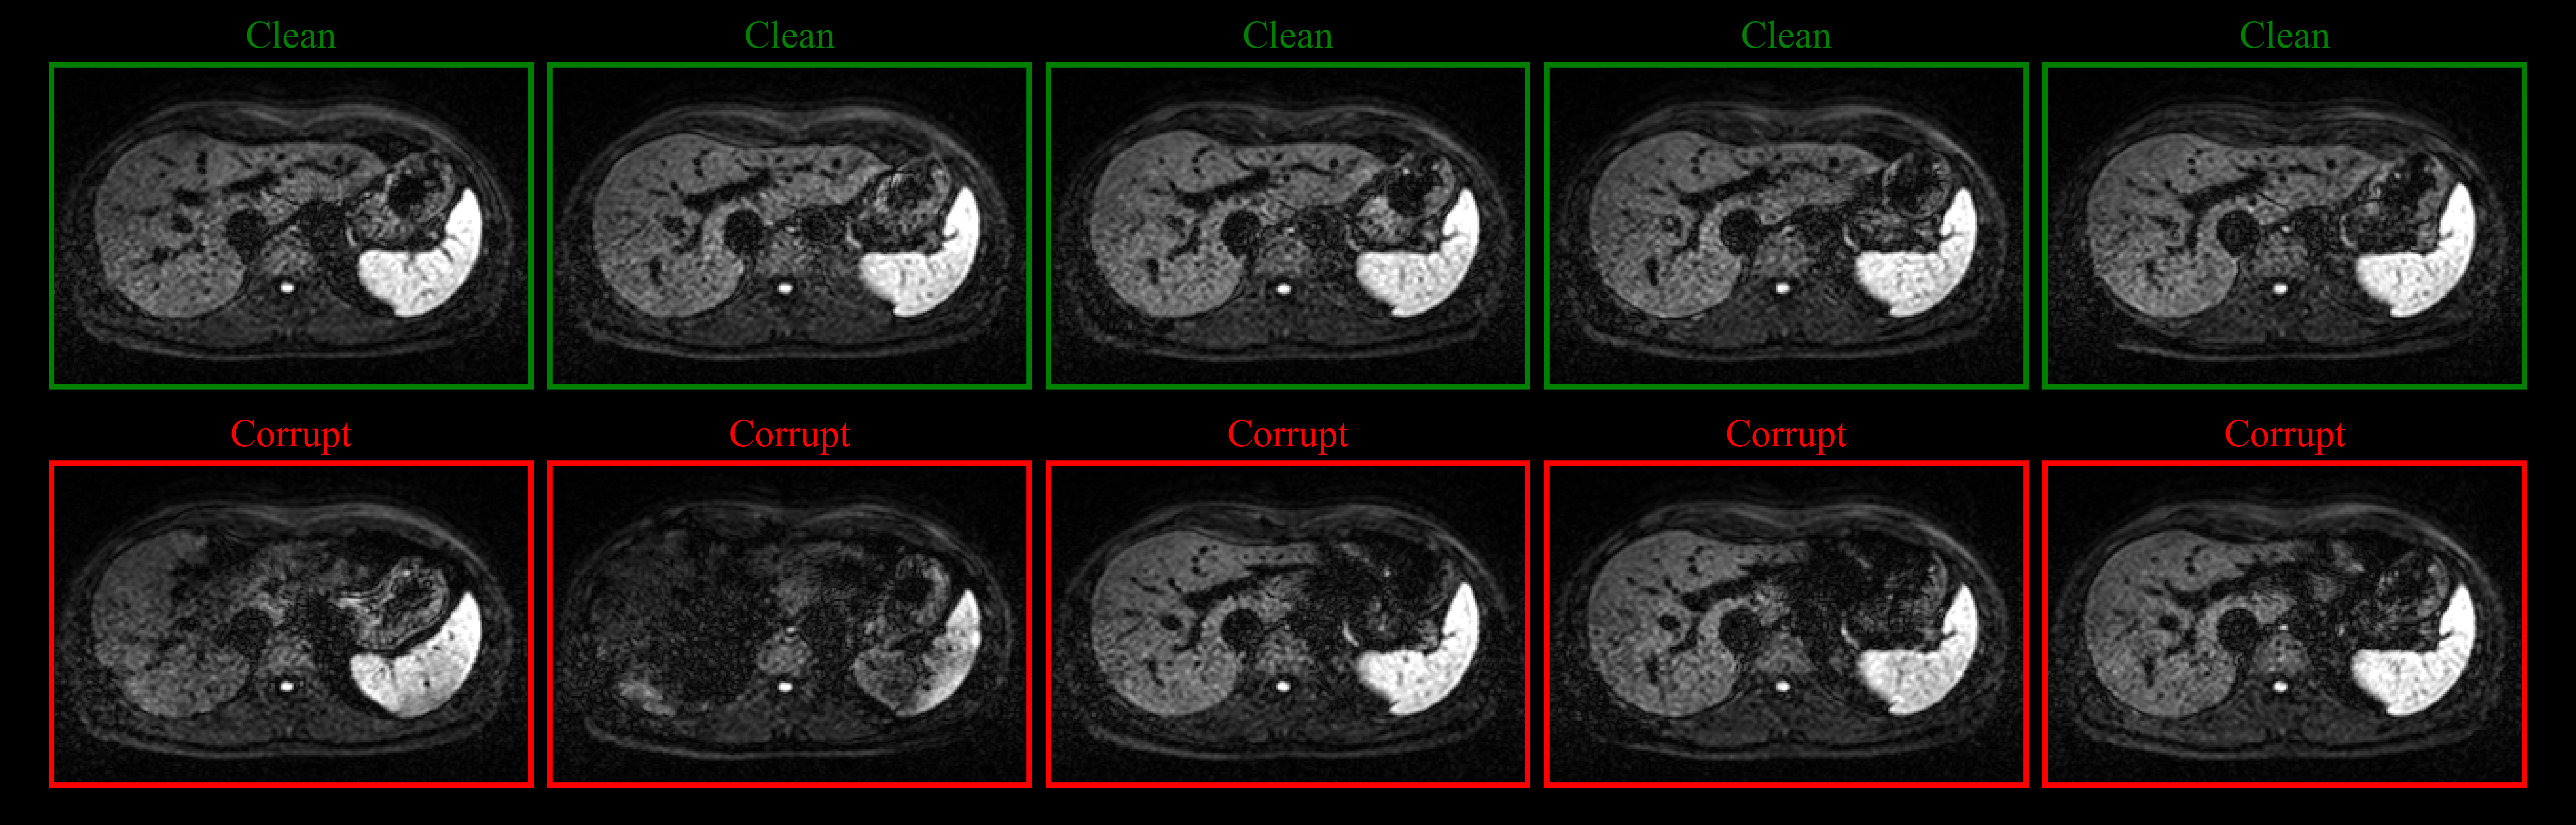

As Figure 8 implies, all three network realizations produce visually appealing reconstructions. However, error images reveal that the image obtained from the network which processes repetitions independently from each other exhibits a higher degree of residual blurring around tissue boundaries and some signal fluctuations (most apparent in the spleen). Using mean or maximum aggregation, both effects can be mitigated. While qualitative differences between the two aggregation approaches are minimal, maximum aggregation results in slightly improved PSNR and SSIM as confirmed by the quantitative evaluation on the whole test set provided in Table 1. As the metrics imply, improvements of joint reconstruction are more substantial for data acquired at b=800𝑏800b=800 s/mm2. Given that a larger number of repetitions is available and individual repetitions are noisier, the greater benefit of joint reconstruction for higher b𝑏b-values conforms to expectation.

Refer to caption

Figure 8: Reconstruction quality of different aggregation techniques on a representative retrospectively PF-sampled (PFF=5/8PFF58\text{PFF}=5/8) liver slice (magnitude average of 20 repetitions acquired at 3 T and a b𝑏b-value of 800 s/mm2). Top row: ground-truth image. Second and third row: reconstructions and corresponding difference images (magnified by a factor of 5) produced by network realizations which use no aggregation, mean and maximum aggregation, respectively.

Since individual repetitions can be affected by imaging artifacts, the effects of those artifacts on the reconstruction of a selected repetition were investigated as well. In the context of DW ssEPI, signal dropouts due to cardiac pulsation are particularly prominent (see Supporting Information Figure S6). Using the proposed reconstruction pipeline with maximum aggregation across the set of image features (DRPFMaxMax{}_{\text{Max}}), a specific repetition was reconstructed in two different configurations in which the remaining 19 repetitions of the set were either affected by signal dropouts (β€˜corrupt’) or not (β€˜clean’), respectively. The results presented in Supporting Information Figure S7 reveal that joint reconstruction with corrupt repetitions can diminish the image quality of the repetition at hand compared to reconstruction with clean repetitions only (βˆ’0.530.53-0.53 dB PSNR, βˆ’0.00660.0066-0.0066 SSIM). However, individual reconstruction of repetitions (DRPFNoneNone{}_{\text{None}}) can still be outperformed considerably (+0.560.56+0.56 dB PSNR, +0.01290.0129+0.0129 SSIM), which substantiates the usefulness of the Deep Set concept regardless of the image quality of individual repetitions.